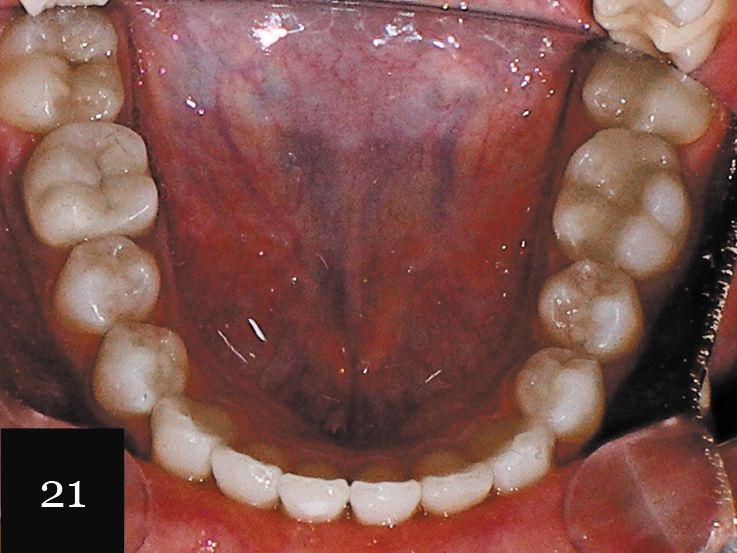

This case demonstrates the outcome of treatment on a young male patient with an anterior crossbite, deep overbite, severe crowding and periodontal disease (Figs. 21 and 22).